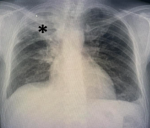

Diagnostic assessment: laboratory tests revealed acute renal failure with a creatinine level of 199 µmol/l and nephrotic syndrome with proteinuria at 11 g/24 hours, albuminemia at 19 g/dl, and proteinemia at 42 g/dl. Renal ultrasound showed two kidneys of normal size with good corticomedullary differentiation. Initially, rifampicin-induced nephrotoxicity was suspected, leading to its discontinuation. Renal function deteriorated rapidly, with levels increasing from 199 µmol/l to 504 µmol/l over 10 days, and hemoglobin decreased to 7.7 g/dl by December 16, 2023. An emergency chest X-ray revealed findings suggestive of pulmonary tuberculosis with signs of activity but no evidence of intra-alveolar hemorrhage (Figure 1). Thoracic computed tomography (CT) showed consolidation with centrilobular branching micronodules, consistent with a tree-in-bud pattern, predominantly affecting the right upper lobe, associated with peribronchovascular thickening (Figure 2). In case of acute nephritic syndrome, we performed autoimmune serologies (ANCA, ANA, anti-GBM antibodies, and complement), which were negative. Serology for hepatitis B and C was negative.

Figure 1: chest radiograph of the patient; right apical and supraclavicular heterogeneous opacities with interstitial and nodular infiltrates (*)